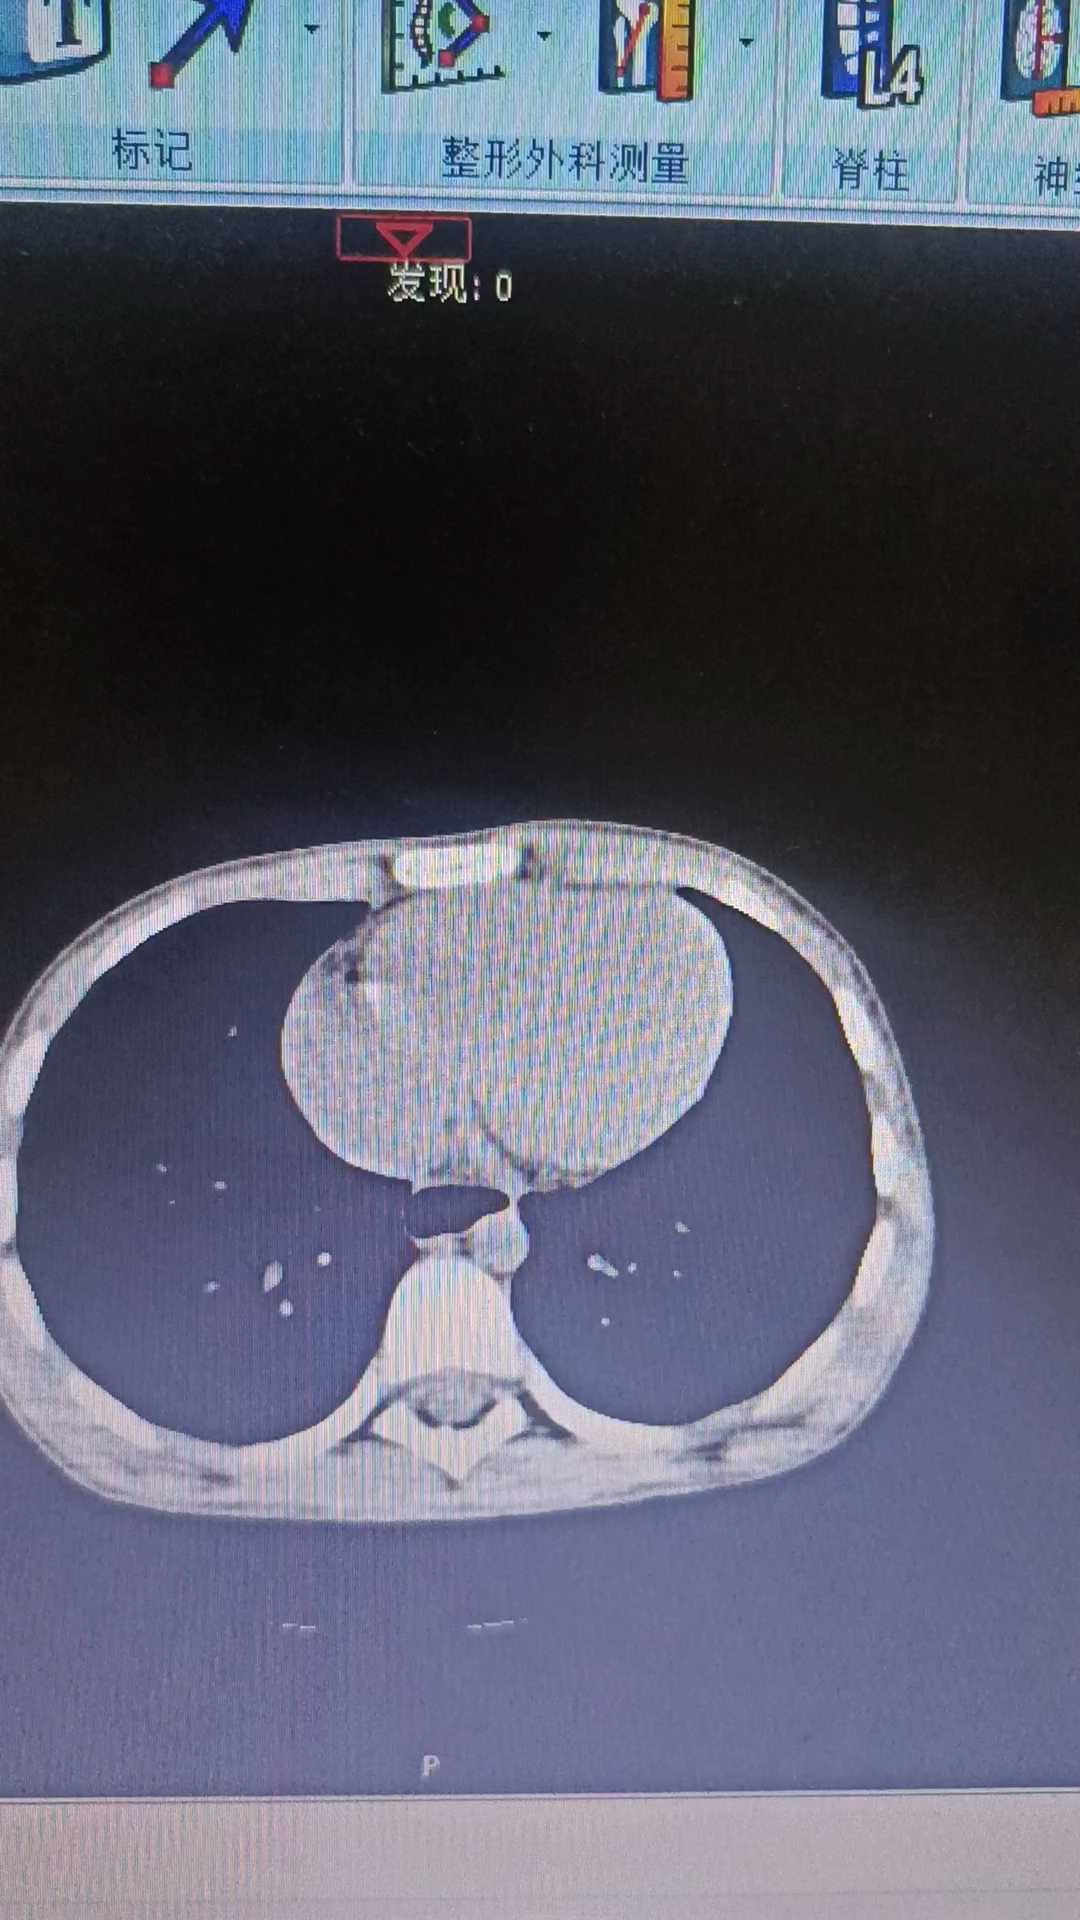

患儿,男,10岁,最近1年间歇性腹胀,无恶心、呕吐,饮食少,逐渐消廋,大便偏干,2-3天排便一次,感觉有排气,无其他不适,查体见腹部稍膨隆,腹壁张力稍大,无压痛,叩诊鼓音,血常规及肝功能正常,今日行腹部CT见腹腔肠管及胃扩张严重。

目前引起患儿腹胀的可能的疾病是什么?需要做哪些方面的检查